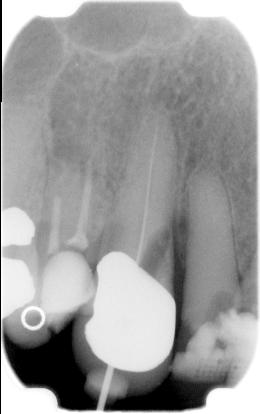

ad f. Een "oude perforatie" heeft een slechtere prognose. Vaak is er al een parodontaal probleem ontstaan welke op een X-foto al te zien is. Voordat een dergelijke perforatie wordt gesloten, wordt eerst gedurende minstens een week

CA(OH)2 ingesloten om de wond “steriel” te maken. Daarna wordt

calciumsulfaat (BoneGen)

aangebracht als matrijs in het perforatiegebied.

Vervolgens wordt de perforatie gesloten zoals hieronder in het schema is beschreven.

Als de vrees bestaat dat MTA wordt doorgeperst omdat er een grote lucentie bij de perforatie zit, dan eerst met snelhardende “steriele” calciumsulfaat (gips, BoneGen) een stop creëren en vervolgens nadat het kanaal opnieuw goed is gereinigd de MTA aanbrengen.